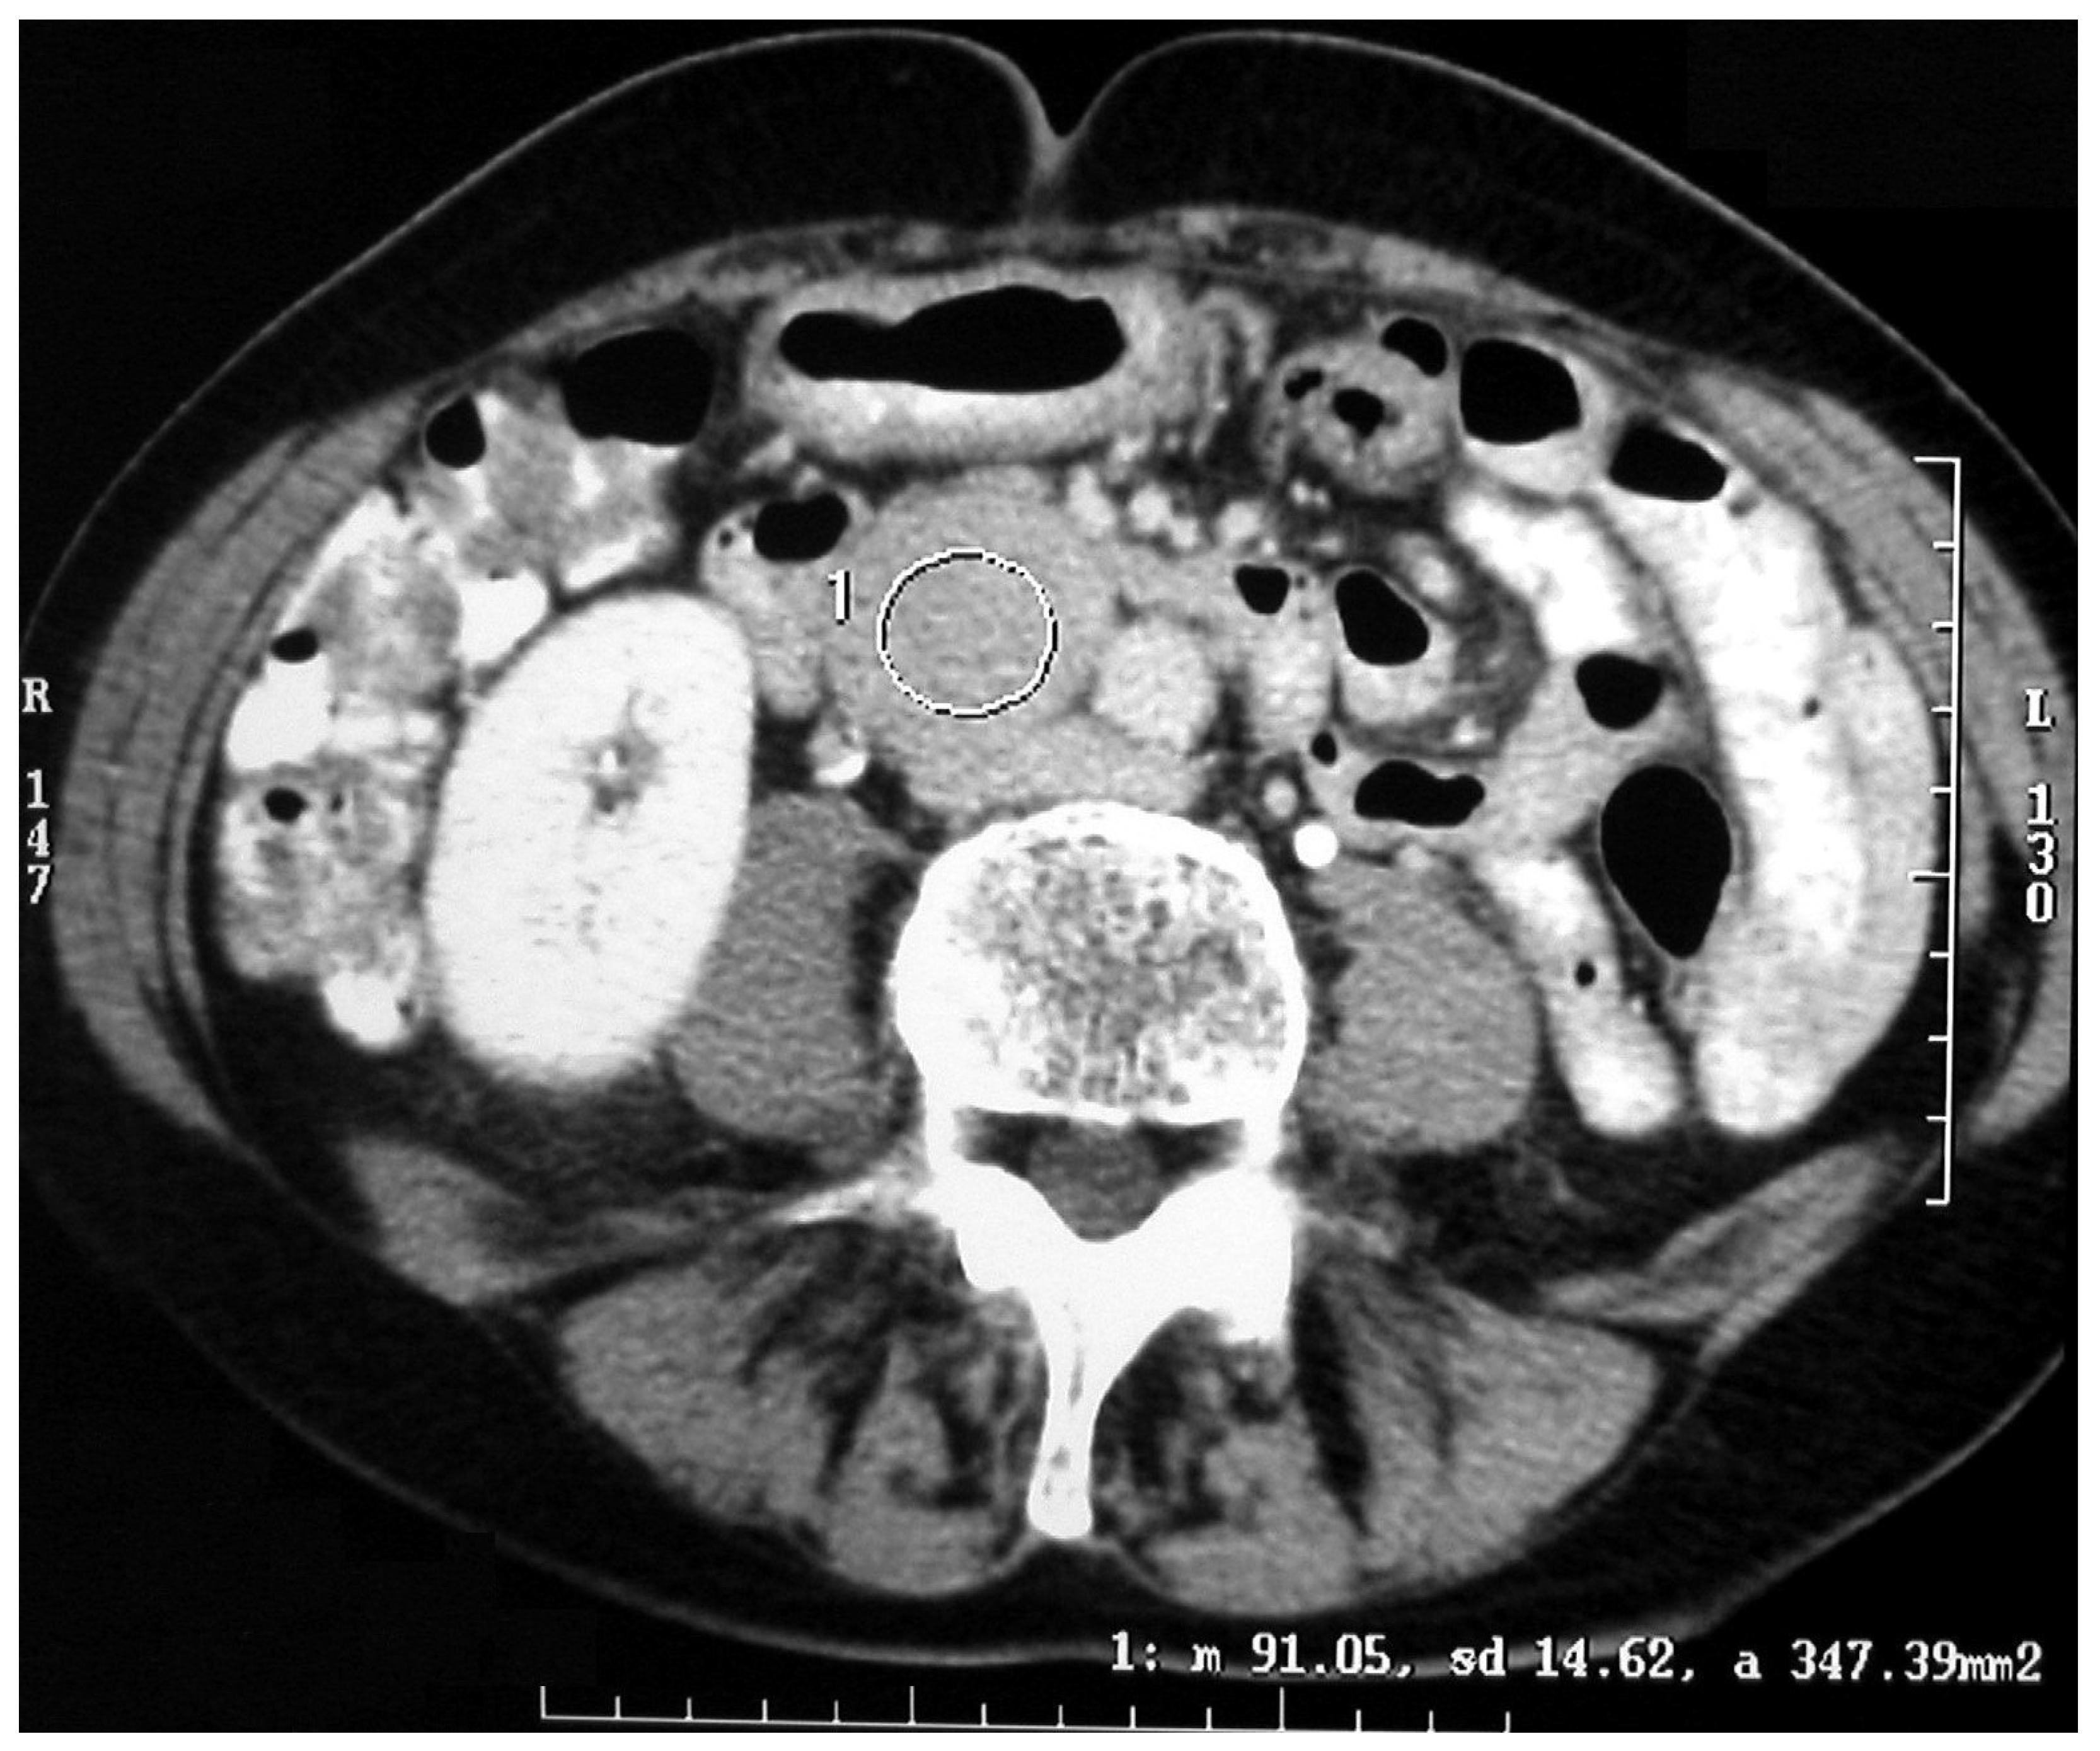

The diagnostic localization of a PCC/PGL is traditionally attempted only once excess catecholamine has been biochemically ascertained [17,18]. Both computed tomography (CT) scanning and MRI are mainstays for adrenal imaging and are used as the primary tests for localizing catecholamine-secreting tumors. CT is the preferred method for its excellent resolution (Figure 3 and Figure 4).

Figure 3. CT scan of an abdominal paraganglioma of above the aortic bifurcation (Zuckerkandl organ’s).